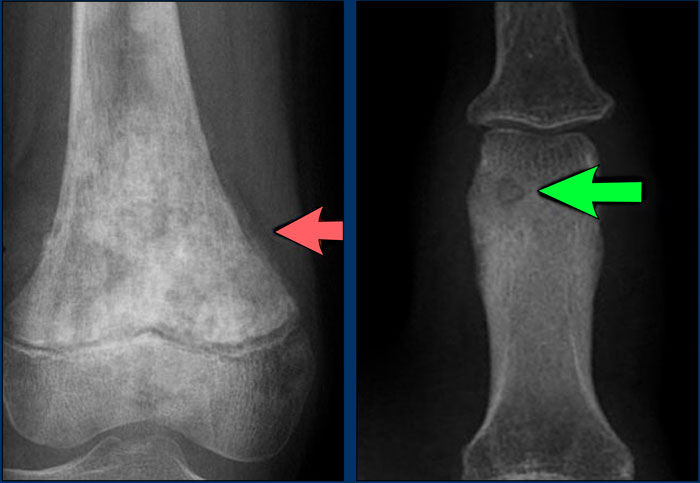

Chondromyxoid fibroma (left), Giant cell tumor (right) Chondromyxoid fibroma (left), Giant cell tumor (right)

Ballooning

Ballooning is a special type of cortical destruction.

In ballooning the destruction of endosteal cortical bone and the addition of new bone on the outside occur at the same rate, resulting in expansion.

This 'neocortex' can be smooth and uninterrupted, but may also be focally interrupted in more aggressive lesions like GCT.

Images

1. Chondromyxoid fibroma

A benign, well-defined, expansile lesion with regular destruction of cortical bone and a peripheral layer of new bone.

2. Giant cell tumor

A locally aggressive lesion with cortical destruction, expansion and a thin, interrupted peripheral layer of new bone.

Notice the wide zone of transition towards the marrow cavity, which is a sign of aggressive behavior (red arrow).